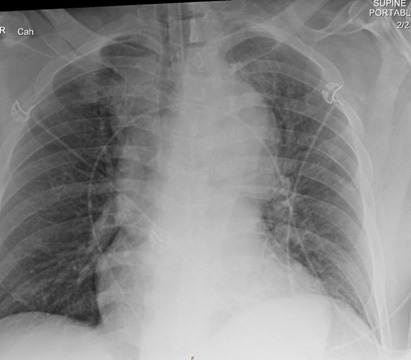

Imaging is the mainstay of diagnosis for aortic dissection or other aortic syndromes. Chest radiograph is a fast mode of initial evaluation. However, X-ray findings of aortic dissection are not reliable for diagnosis, and this evaluation is not sufficient to rule out acute aortic syndromes. The most common finding with acute aortic dissection on the chest radiograph is mediastinal enlargement, assessed to be about 54% sensitive and 92% specific.27 (See Figure 1.) Most patients presenting with acute dissection will have some abnormality on chest radiograph, so for this reason, it is a good initial imaging study to confirm the need for additional advanced imaging. However, because of the low sensitivity, it is not appropriate to rule out dissection. Also, the chest radiograph can be used to ensure that there is no additional pathology or complication contributing to the patient’s presentation, such as pneumothorax, hemothorax, or pneumonia.

Figure 1. Chest Radiograph with Wide Mediastinum |

![]() |

Image courtesy of Daniel Migliaccio, MD |